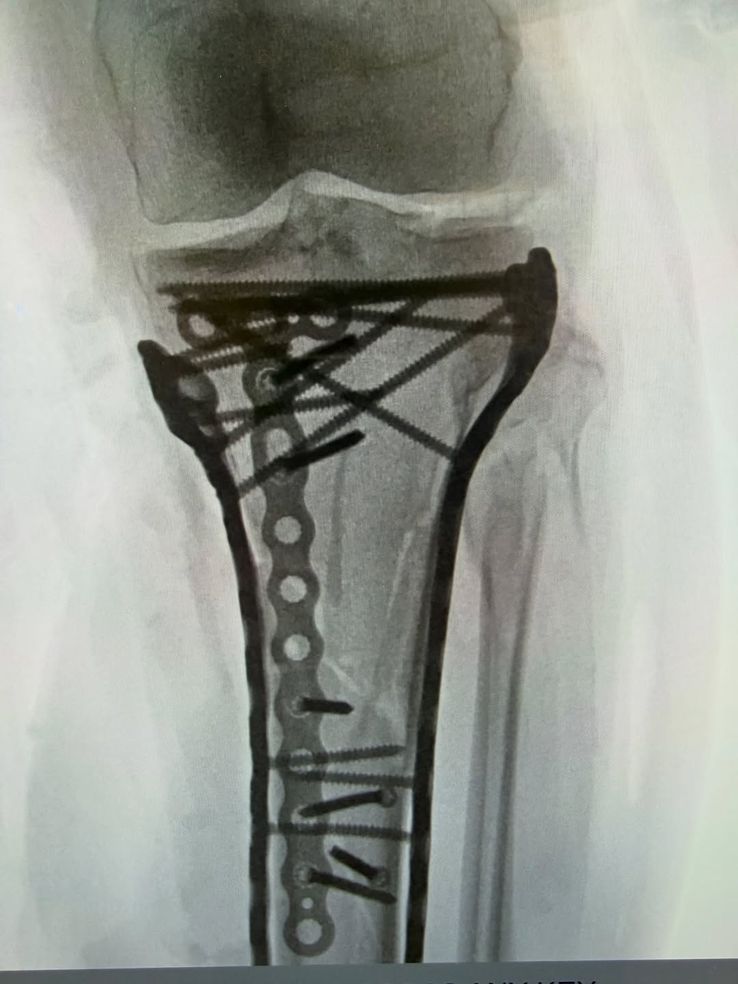

„Am trecut cu bine de operație... a durat puțin peste 6 ore. După cum puteți vedea, a fost nevoie de o mulțime de plăcuțe și șuruburi pentru a pune totul la loc, dar Dr. Hackett a făcut o treabă incredibilă. Îi mulțumesc și Dr. Viola pentru asistența acordată în timpul intervenției!!

Din imaginile publicate de Vonn reiese că a fost nevoie de o reconstrucție majoră pentru ca piciorul să-i fie stabilizat. Medicii au utilizat o placă metalică lungă și undeva până în 20 de șuruburi dispuse în diferite unghiuri.

Piciorul lui Lindsey Vonn după operația din 20 februarie // foto: Instagram